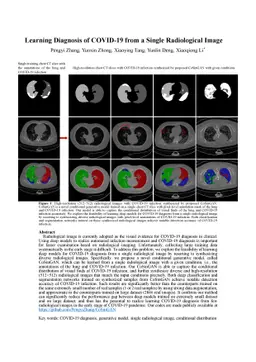

Learning Diagnosis of COVID-19 from a Single Radiological Image

Pengyi Zhang

Yunxin Zhong

Xiaoying Tang

Yu-Cheng Deng

Xiaoqiong Li

MedIm

155

8

0

06 Jun 2020